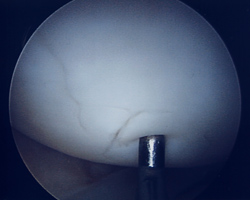

Abb. 5: 4° Knorpelschaden nach ICRS an der Kniescheibe

Abb. 6: Knorpelschaden wurde durch einen Knorpel/Knochenzylinder ersetzt

Eine andere Behandlungsoption stellt die Transplantation eines Knorpel-Knochenzylinders dar. Hierbei kann der Operateur aus einem unbelasteten Bereich des Gelenkes mittels einer speziellen Diamant-Hohlfräse einen Zylinder entnehmen und diesen in den Knorpeldefekt einfügen, in den dieser dann einheilt. Auch bei diesem Verfahren ist eine postoperative Entlastung notwendig.